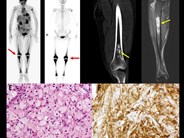

Erdheim-Chester Disease-CD68

Category: Macrophage/Histiocytic and dendritic cell Neoplasms and disorders (2015) > L group > Erdheim-Chester disease